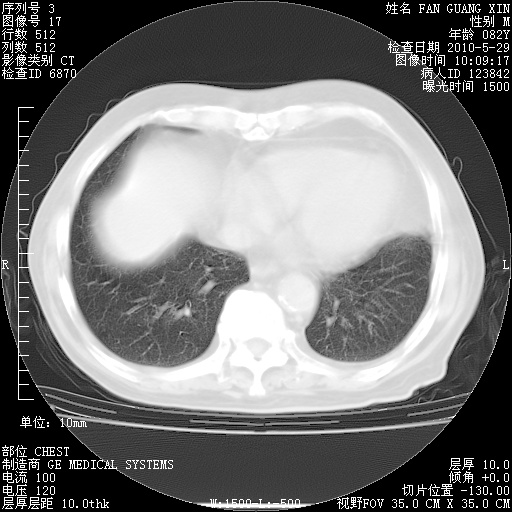

再治疗10天后的肺部CT 纵膈窗